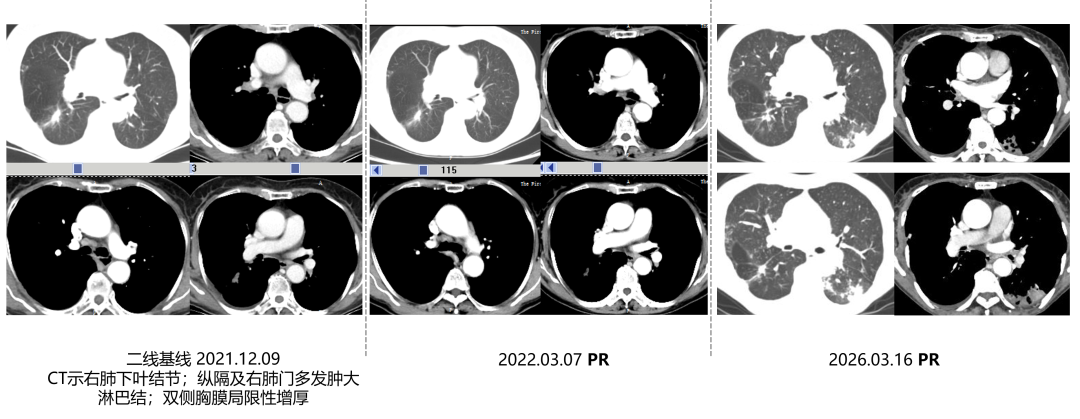

2022年12月8~9日,筛选期检查,确诊肿瘤分期:T2N3M1a,Ⅳa期。

CT检查:右肺下叶结节;纵隔及右肺门多发肿大淋巴结;双侧胸膜局限性增厚;肿瘤最大径1.65cm。

2022年3月7日:复查CT达到部分缓解(PR),维持至今*,PFS超49个月。

二线治疗前后影像对比

*至今:最近一次随访时间,2026年3月16日。